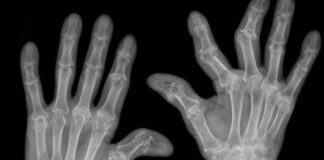

Artrite reumatoide, i rischi del sovrappeso